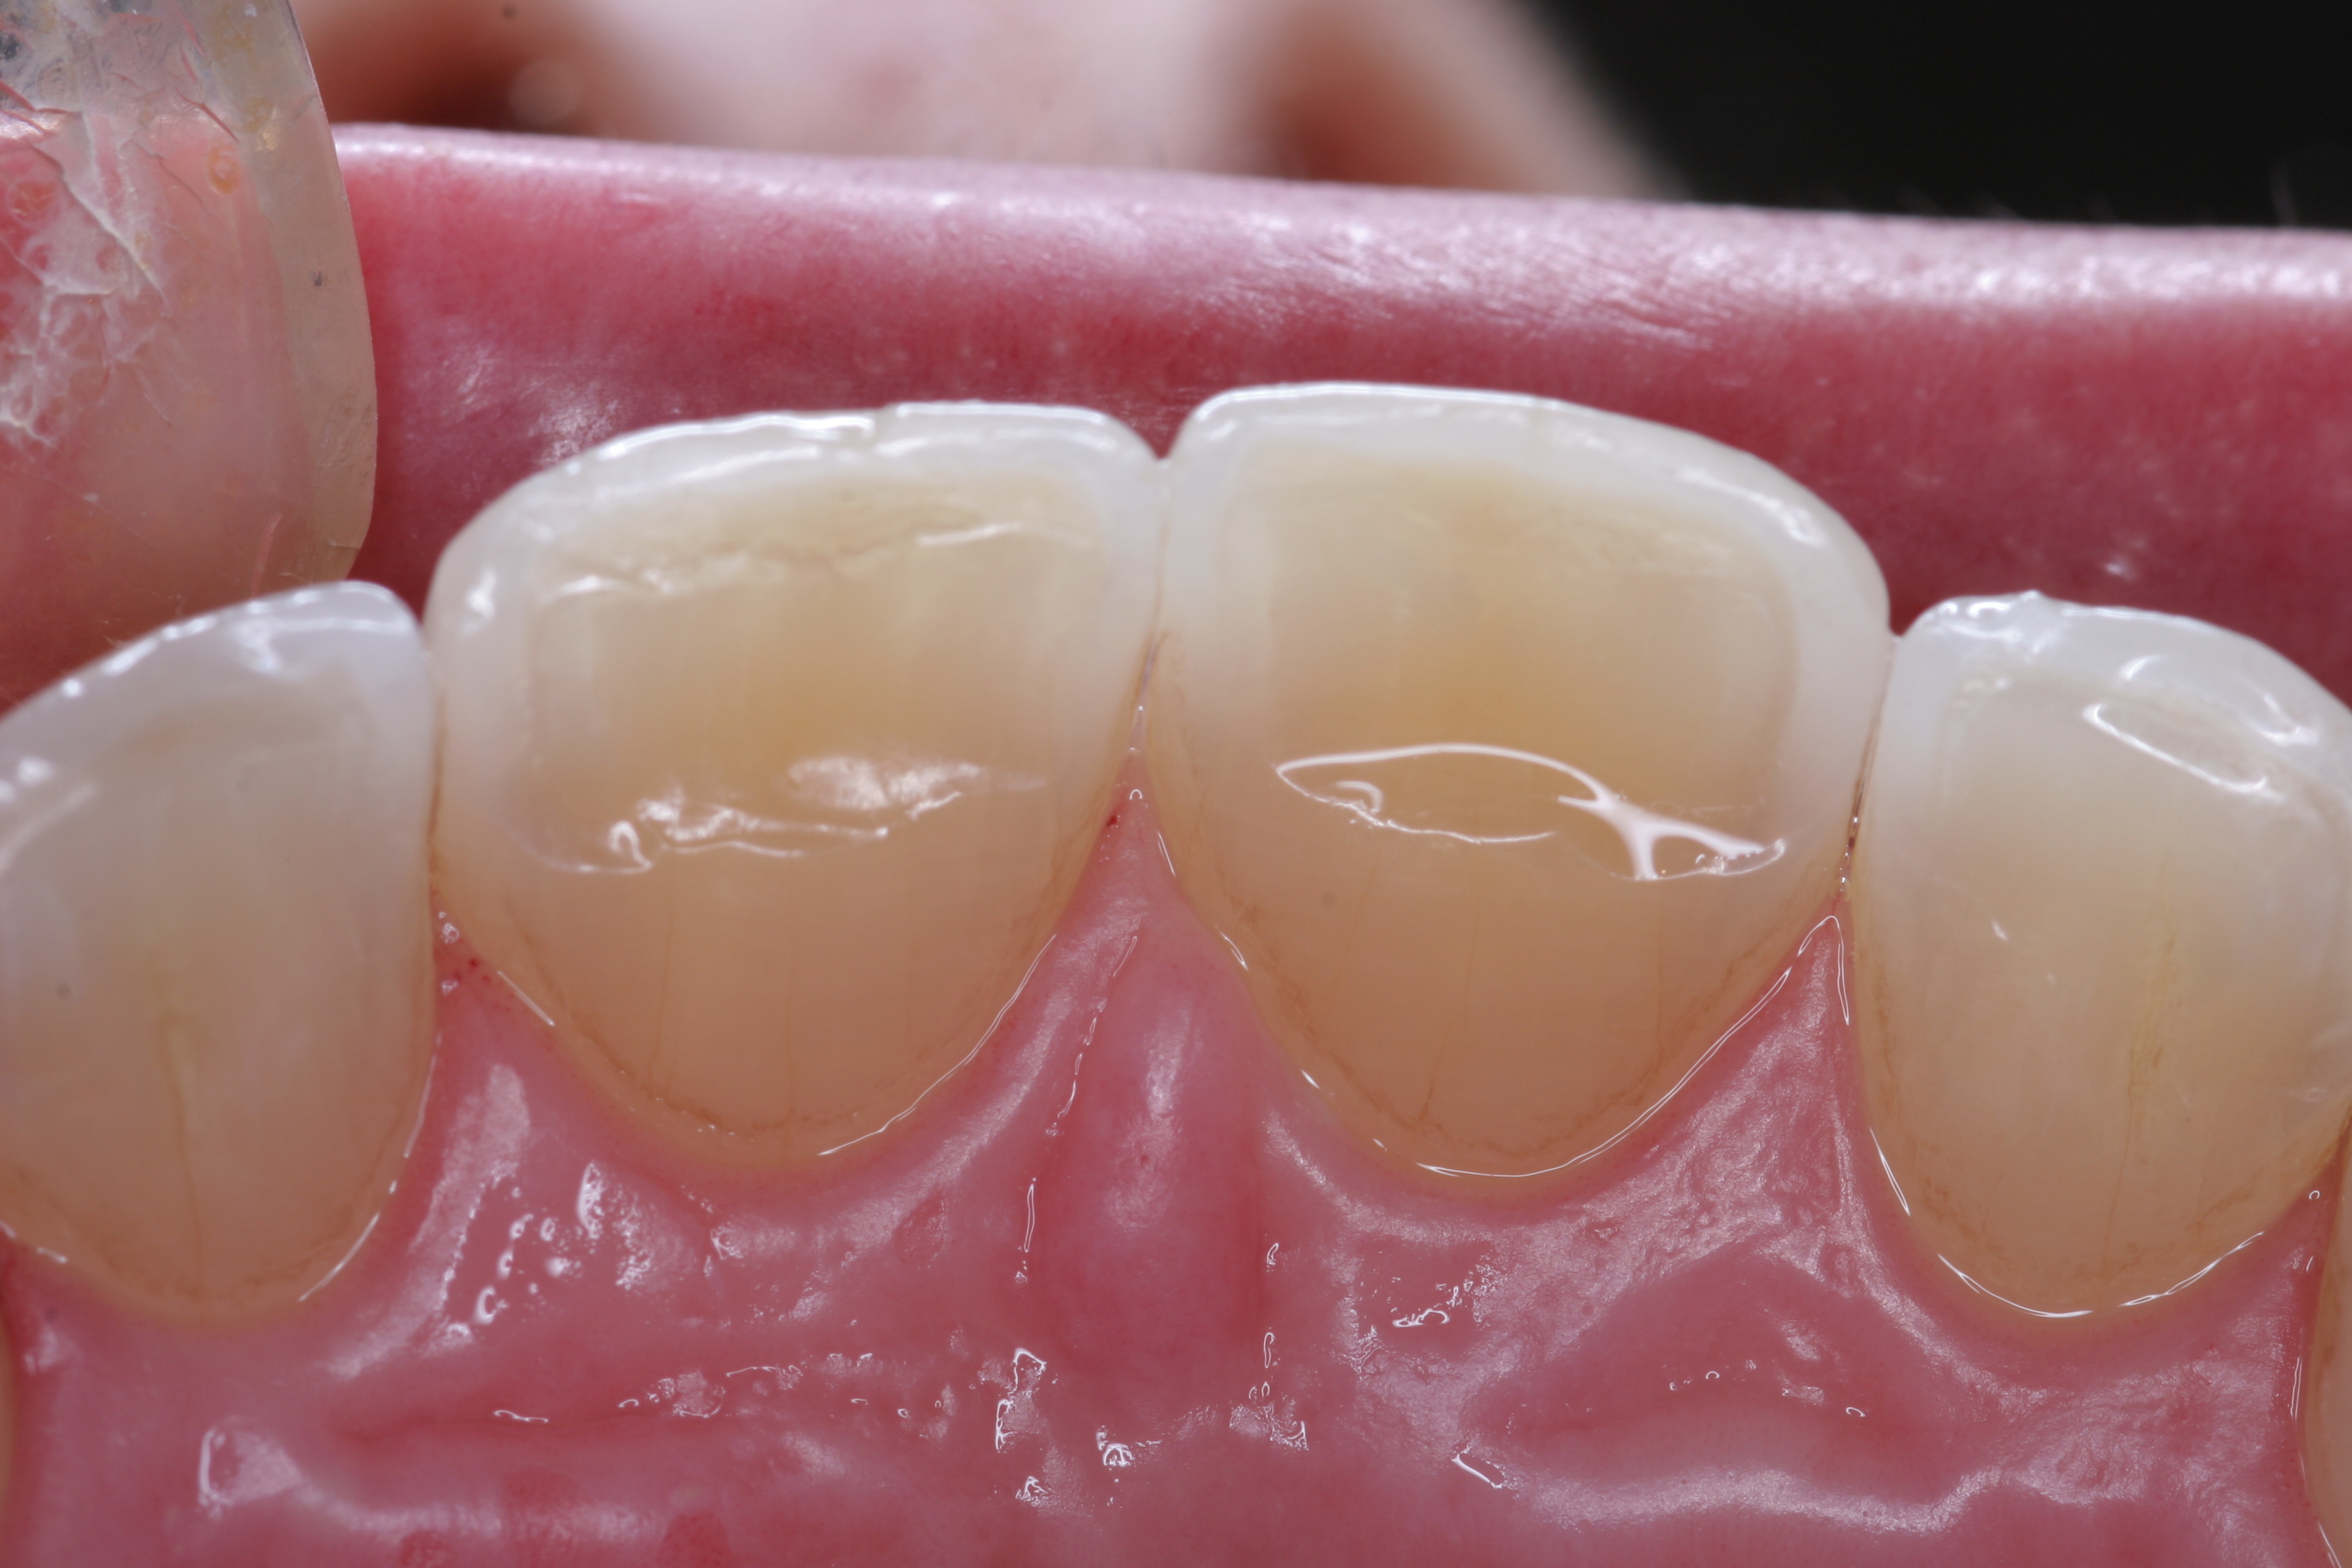

(22.) The final restorations, which reflect the changes modeled through the provisional phase.

Figure 22

(23.) The final restorations, which reflect the changes modeled through the provisional phase.

Figure 23

(24.) The final restorations, which reflect the changes modeled through the provisional phase.

Figure 24

(25.) The final restorations, which reflect the changes modeled through the provisional phase.

Figure 25

(26.) The final restorations, which reflect the changes modeled through the provisional phase.

Figure 26

(27.) The final restorations, which reflect the changes modeled through the provisional phase.

Figure 27

(28.) The final restorations, which reflect the changes modeled through the provisional phase.

Figure 28

(29.) The final restorations, which reflect the changes modeled through the provisional phase.

Figure 29

Once approved, impressions of the provisionals were taken so the laboratory could precisely copy the 3D position of the anterior teeth as successfully proven in the provisionals. The postoperative result and final functional photographs are shown in Figure 22 through Figure 29. Posterior treatment can now be completed in segments as necessary. Posterior morphology will be developed in harmony with the now corrected anterior contour and functional parameters. The fulfillment of the previously mentioned requirements of occlusal stability were evaluated and refined in the final restorations. The patient was placed in a posttreatment dual-arch B splint appliance to help manage any further parafunctional forces should they occur.